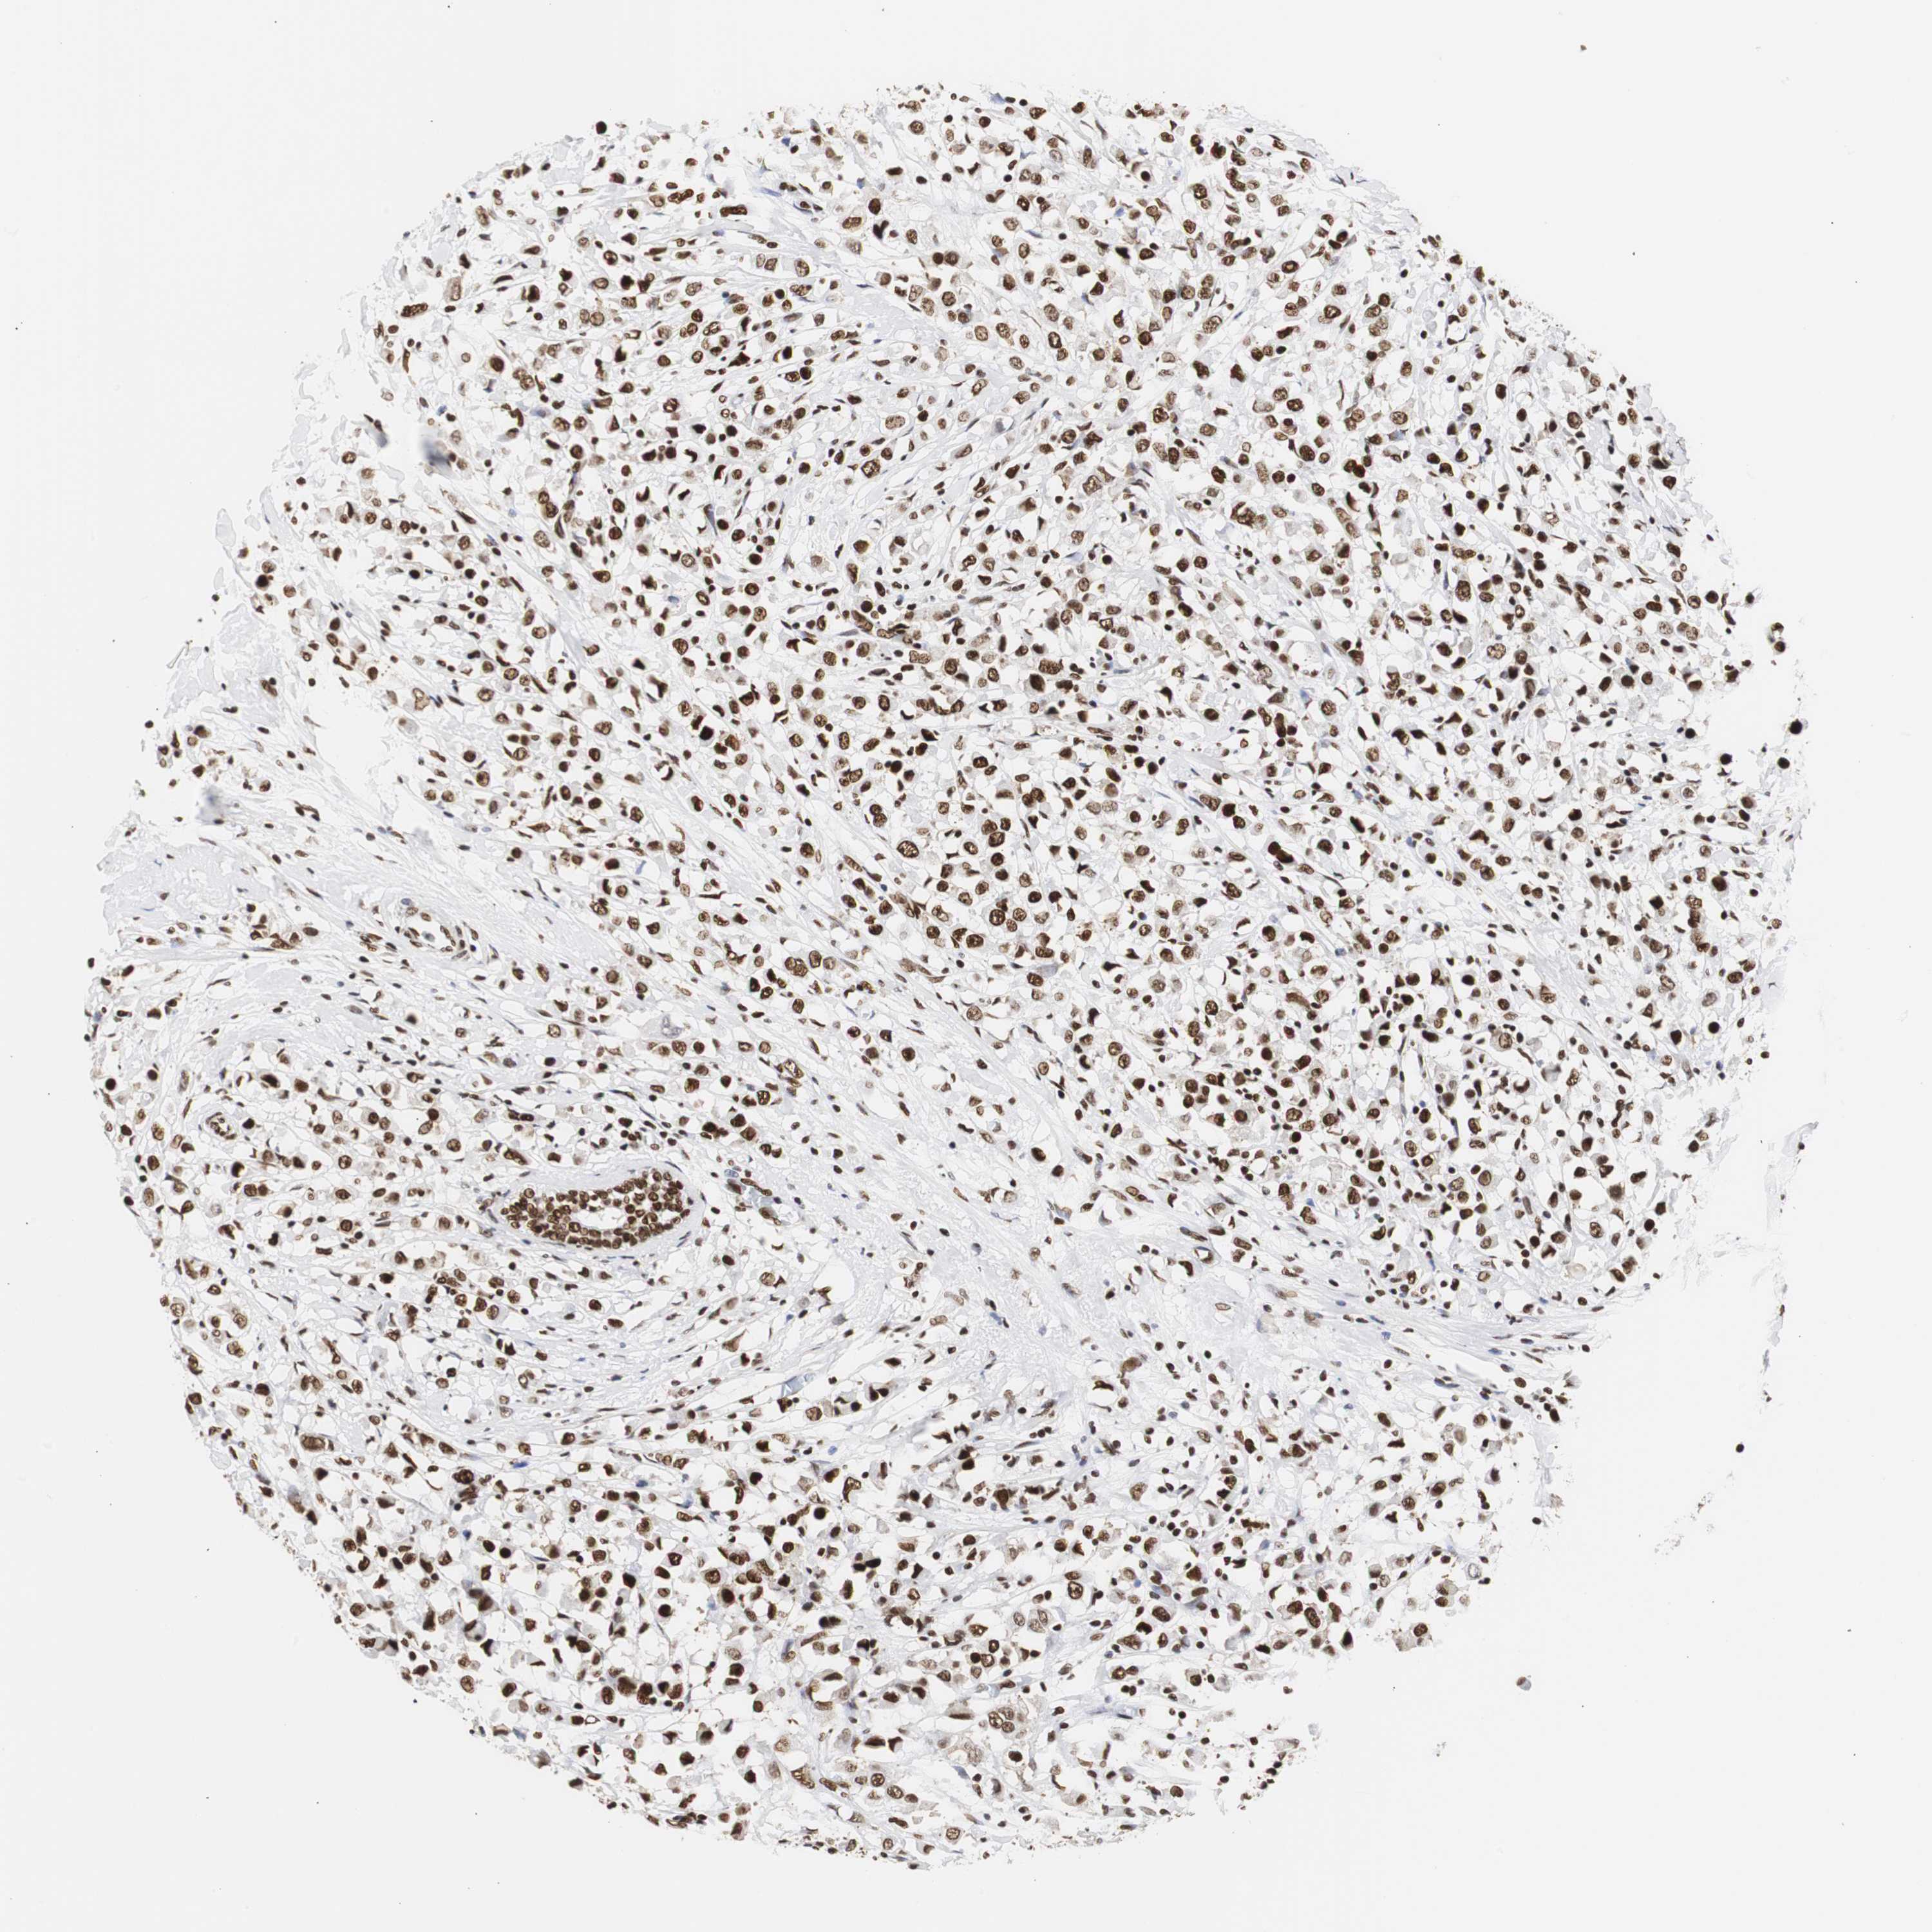

CANCER BREAST CANCER Show tissue menu

BRCA TCGA BRCA VALIDATION PROTEIN EXPRESSION